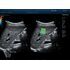

Программное обеспечение для оценки эластичности ткани методом эластографии сдвиговой волны (метод 2D-с формированием двухмерной цветовой эластограммы и количественной оценкой эластичности) на линейных и конвексных датчиках.

STE интегрирована с эксклюзивной технологией Ultra-Wide Beam Tracking от Mindray для двумерной эластографии сдвиговой волной в реальном времени. Специализированные измерительные инструменты позволяют проводить количественный анализ модуля упругости с высокой точностью.